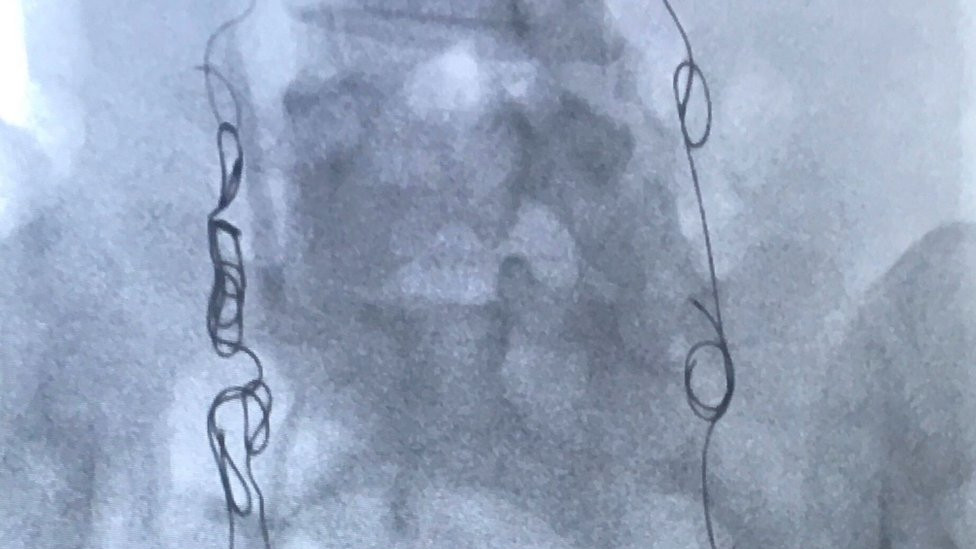

Utorak je, 14. avgust 2018. godine, a ja sam pod anestetikom, ležim na operativnom stolu, dok se metalni kalemi ubacuju u moje vene jajnika i karlice preko katetera u mom vratu.

Emobilizacija koju sam imala 2. avgusta 2018. godine blokirala je moje zakrčene vene metalnim kalemima da ne mogu više da se pune krvlju, uvećavaju i nanose mi bol.